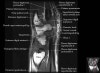

- Sagittal section

Sagittal T1 evaluates the tendons, bone marrow and relationships between the osseous structures.